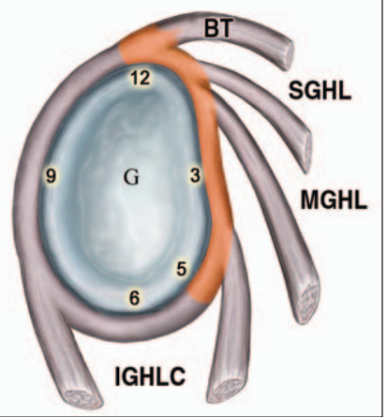

▶ SLAP lesion 4type

- 제1형 : 관절와순은 관절와에 부착되어 있으나 마모 및 변성이 있는경우(이두장건 부착부는 분리되지 않은 상태)

- 제2형(가장 흔한 유형) : 관절와순 및 이두장건의 박리가 있는경우(이두장건 부착부위가 파열되어 일부 분리)

- 제3형 : 양동이 손잡이 파열로서, 상부관절와순이 파열되어 관절안으로 전위되었으나 이두장건 부착부위는 손상이 없는경우

- 제4형 : 상부관절와순의 파열이 이두장건까지 연장되어 있으며 관절안으로 전위되어있는경우로서 드문 유형입니다.